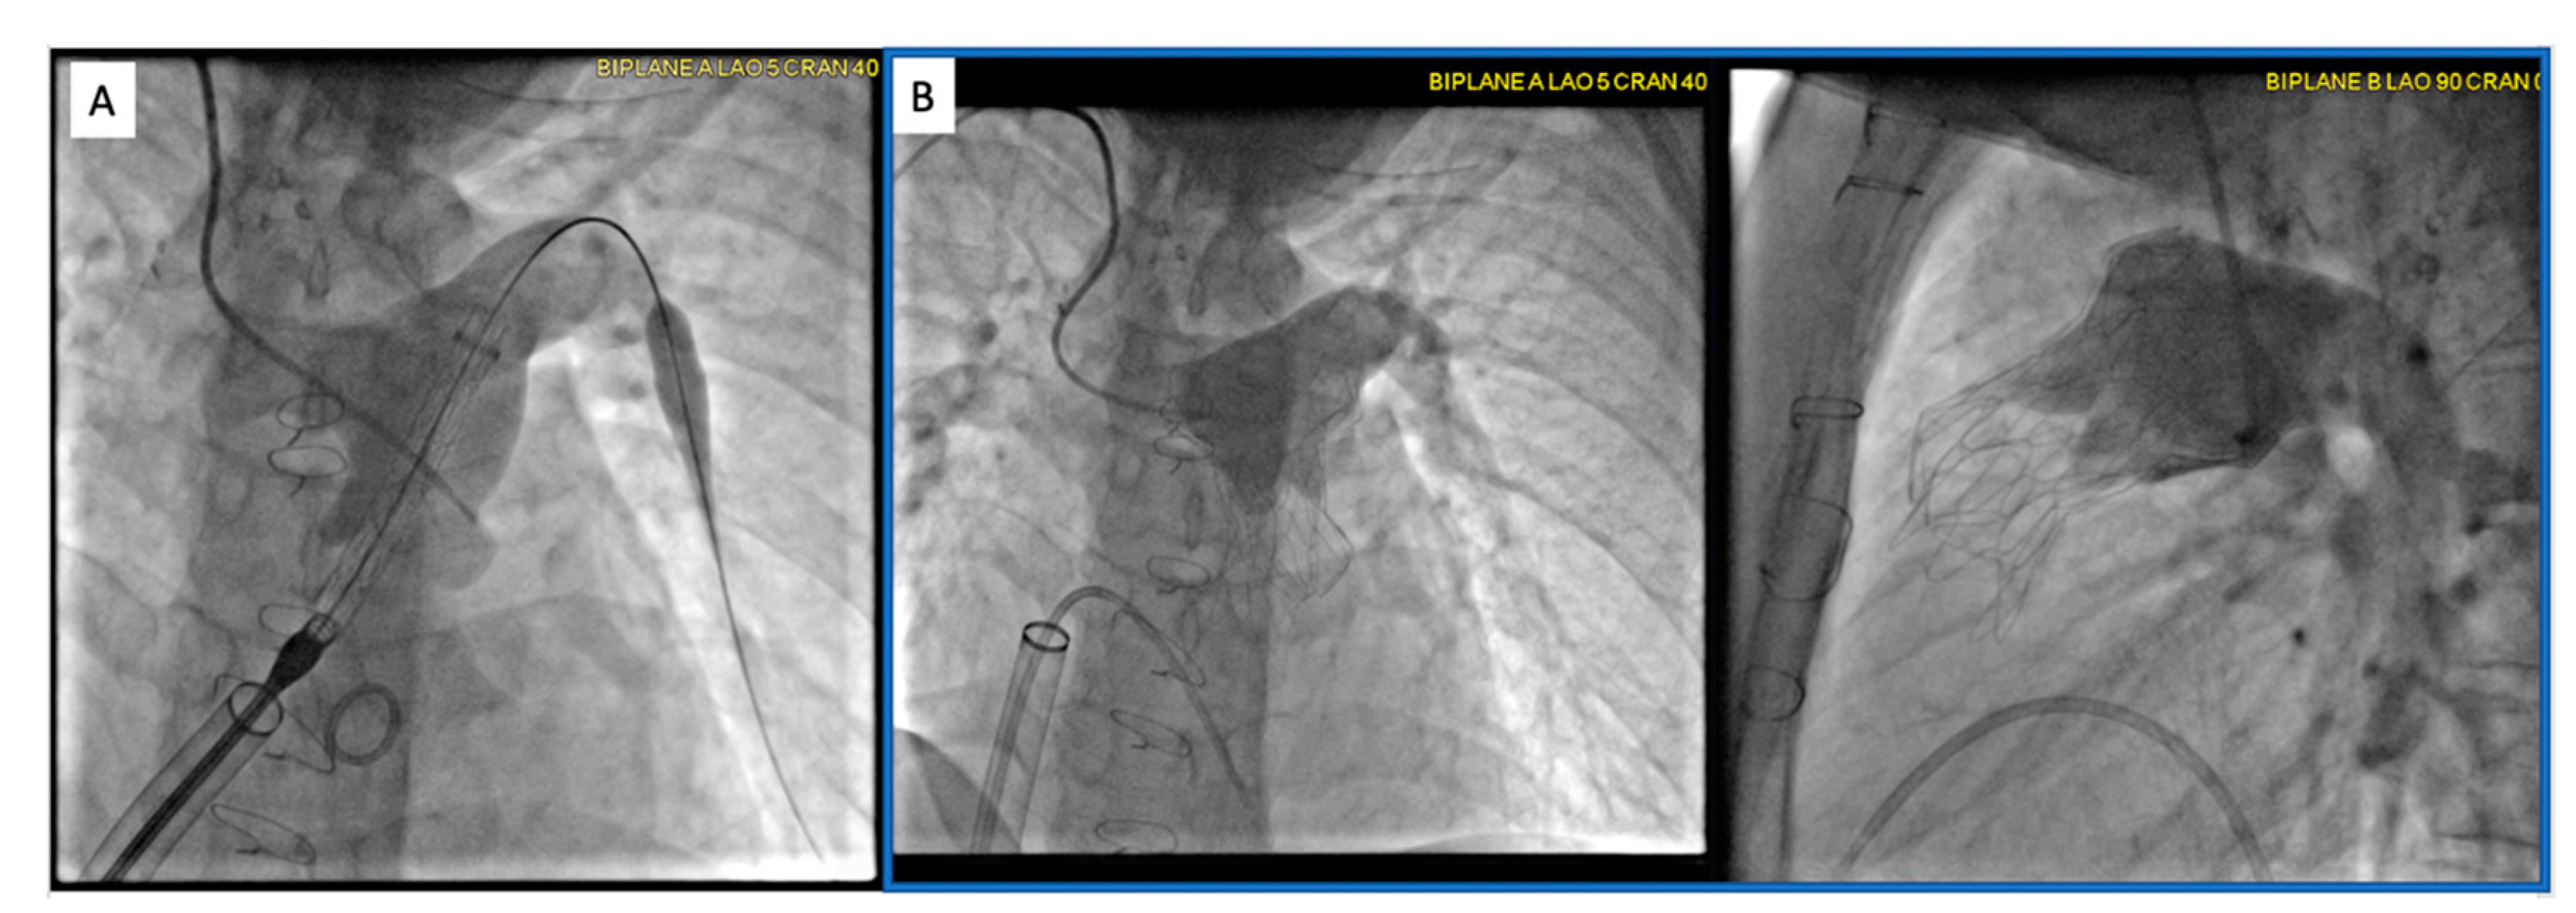

2.2. Patent Ductus Arteriosus (PDA) Stenting for Ductal-Dependent Pulmonary Blood Flow

2.2.1. Pre-Procedural

2.2.2. Post-Procedural